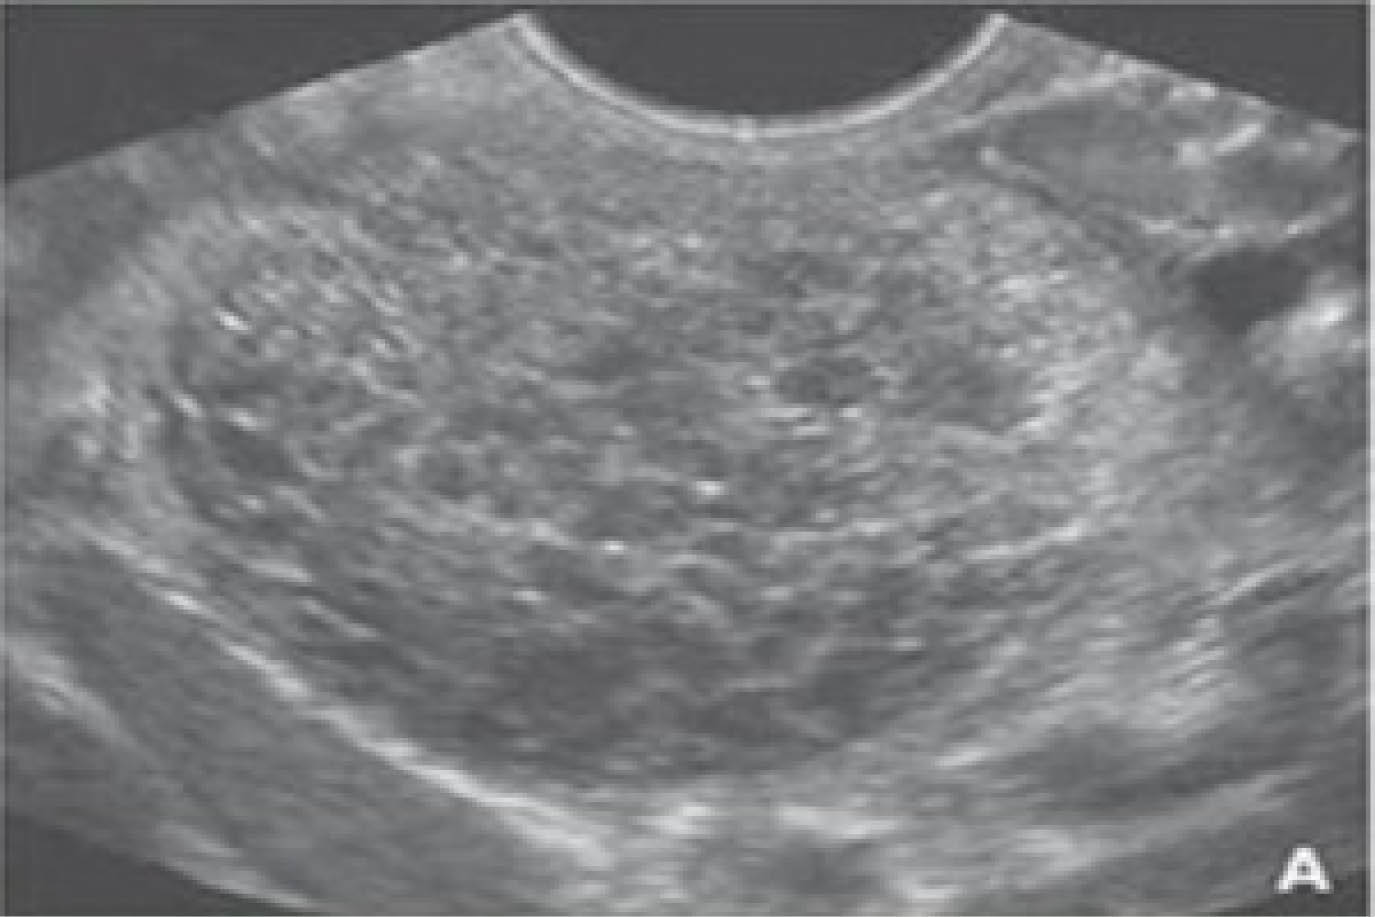

En los pacientes en que se sospecha IPH inicial se observa con la ultrasonografía, siendo un método no invasivo y una observación en tiempo real del hígado, así como la hemodinámica hepática, en conjunto con el medio de contraste Sounazoid el cual da mejores imágenes y dando microburbujas que ayuda a la distinción de problemas hepáticos.

Para la valoración se utilizó un transductor convexo de 3.75 MHz. Primero se utilizó un ultrasonido en escala en grises, realizando una exploración intercostal derecho para observar el lóbulo hepático derecho y la imagen de la vena porta derecha, en promedio con tiempos entre 10 y 15 minutos, siendo en los sujetos control de 12 minutos y de 20 minutos en pacientes con cirrosis para la adecuada evaluación ultrasonográfica.

A los pacientes que se les sometió a la aplicación del medio de contraste para la mejor observación del lóbulo hepático derecho, al momento de la revisión ultrasonográfica se pudo observar que las imágenes tenían mayor intensidad  en los pacientes con cirrosis; no hubo diferencia significativa entre las imágenes en los pacientes con IPH y sujetos control